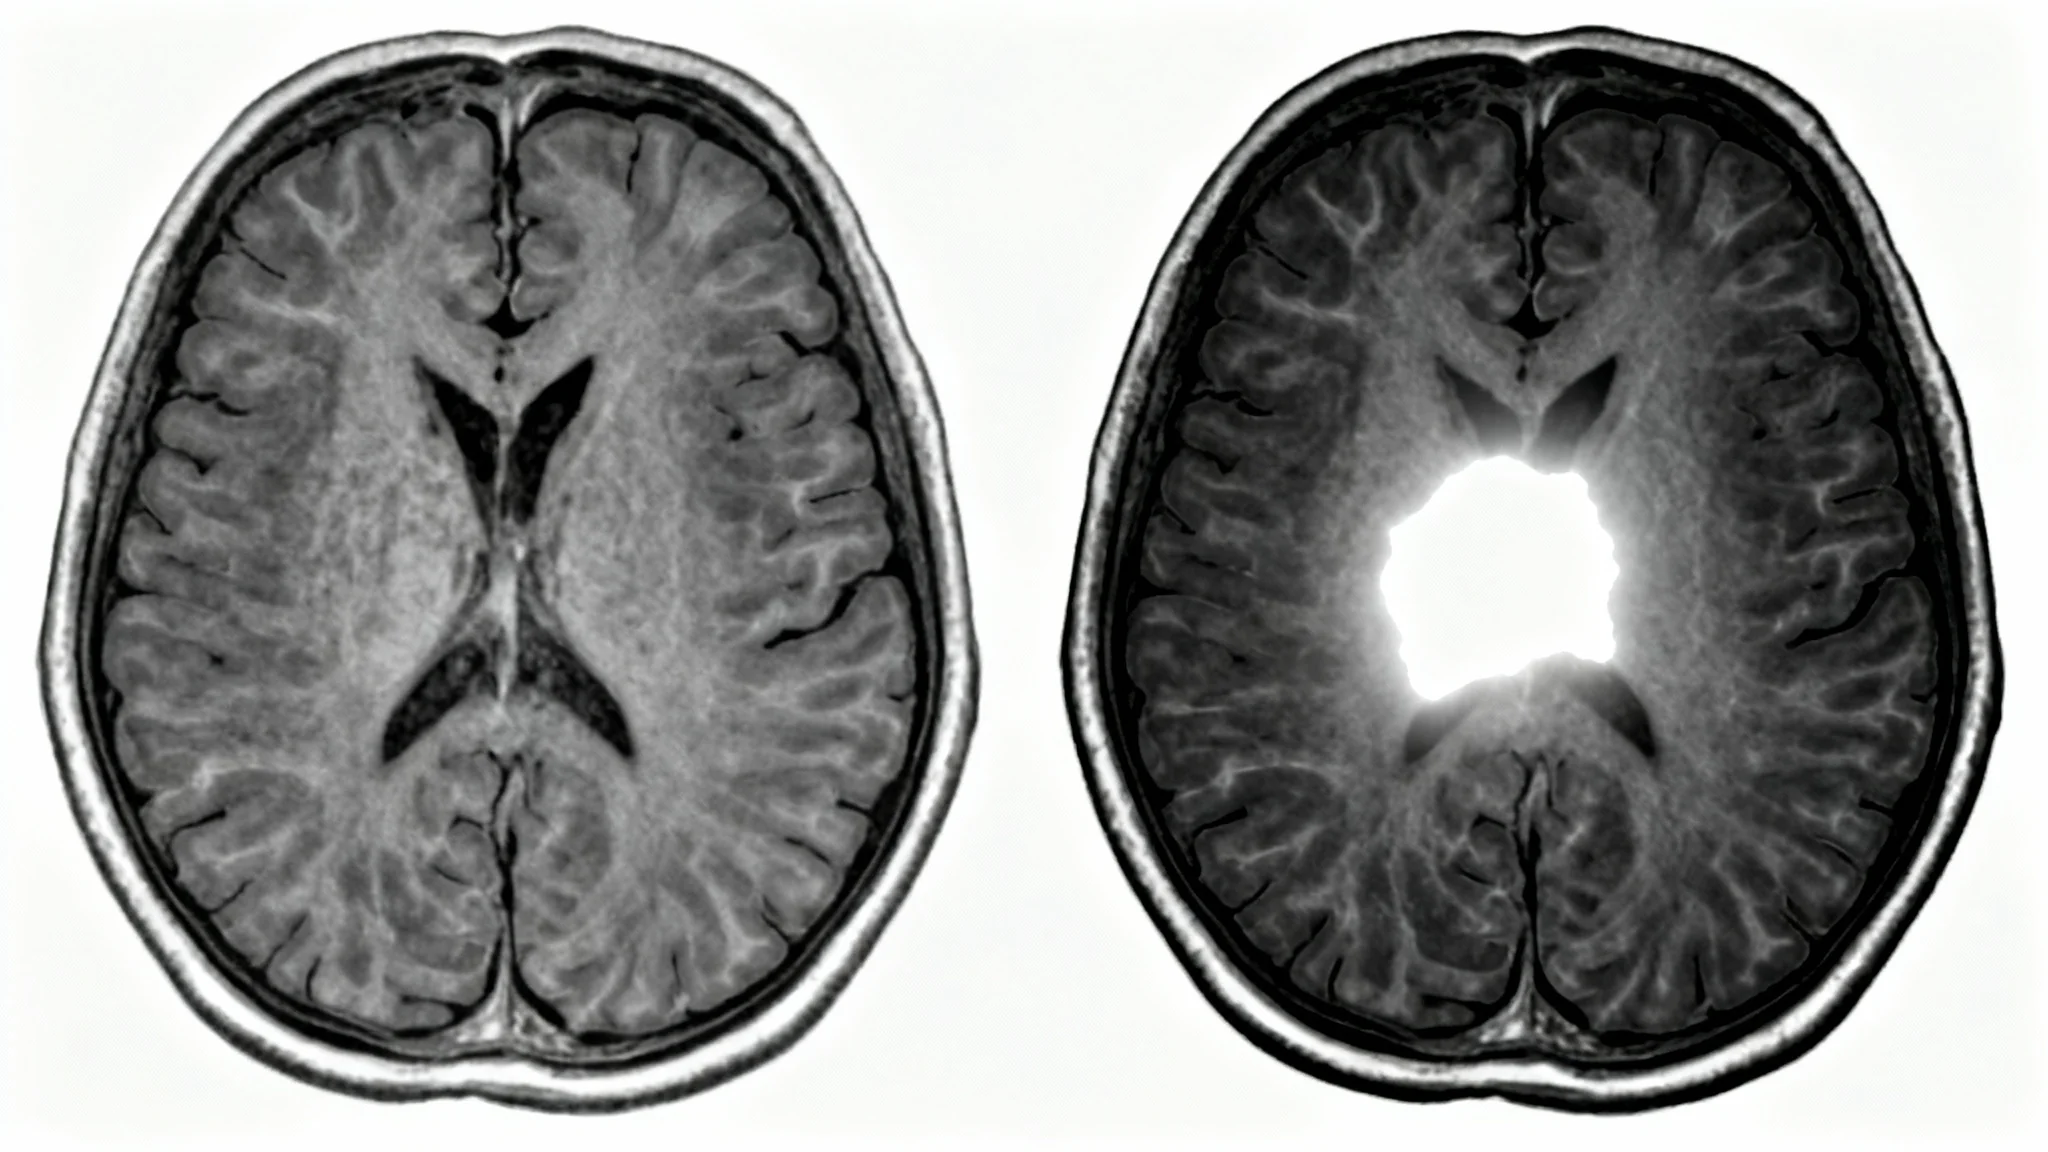

A side-by-side comparison of an MRI brain scan. The left image is a standard, low-contrast scan. The right image is a high-contrast, enhanced version, showing sharp details and highlighted areas, illustrating the effect of MRI contrast enhancement.

Reduce the time spent on manual image adjustments and post-processing. Pixelcut’s AI agent streamlines the enhancement process, delivering a high-quality, contrast-enhanced scan in moments. This efficiency allows medical professionals to focus more on analysis and reporting rather than on image manipulation. By automating a key step in the imaging pipeline, our tool helps accelerate the entire diagnostic workflow, from scan acquisition to final report, enabling faster delivery of crucial information.